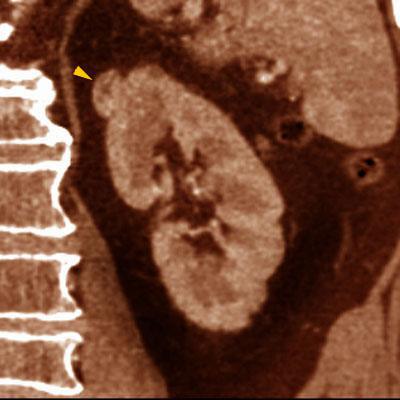

Oncocitoma

VR seccional Visión sagital derecha. Estudio contrastado que muestra una pequeña lesión cortical, sólida, bien definida (punta de flecha), con lesión hipodensa central cicatrizal